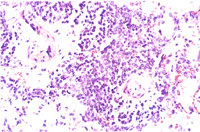

組織病變: 肺臟部份區域可見圍小支氣管及圍血管周圍淋巴組織增生(圖3),這些細胞以淋 巴球及少量巨噬細胞和漿細胞為主(圖4)。

其它病變可見第二型肺泡細胞增生,小支氣管上皮細胞肥大增生,小支氣管擴張, 肺泡間隔淋巴球及漿細胞等浸潤。

黴漿菌症為大小鼠首要病原,而且可藉由空氣或接觸感染,一旦發生,其難滅絕。 黴漿菌有20多種血清型,而一般會造成人或囓齒類感染為:M. collis : 非致病性,存在於大小鼠之鼻咽部及結膜,亦有報告指出會造成生殖道感染。 M. arthritidis : 大鼠關節炎。 M. neurolyticum : 小鼠旋轉病。 M. pulmonis : 鼠類及兔子重要呼吸道傳染性病原。為大小鼠首要呼吸道病原其鑑別診斷見表一。 M. pneumoniae : 人類非典型肺炎。 M. hominis : 人類婦女生殖道感染。 而人鼠之間不同的黴漿菌亞型,一般而言並不會互相感染,亦即並非人畜共通疾病。 大鼠對黴漿菌較敏感,而報告指出不同的菌種中以上M. pulmonis 具顯著呼吸道致病性。患鼠出現體重減輕、呼吸困難或呼吸道震顫聲。一旦環境中氨濃度高過25ppm以上或病毒(Sendai,MHV)合併感染則會加重黴漿菌感染之疫情。感染途徑可經空氣傳播、子宮感染及接觸等方式。臨床症狀有時在感染後 3~6個月才出現。病變一般呈不顯性或輕度症狀,鼻腔、呼吸道、中耳、子宮是檢查重點。肉眼可見化膿性鼻炎、肺前腹端肝變、支氣管擴張、肺膿瘍或中耳炎。組織相特徵為呼吸道上皮細胞扁平化生,纖毛消失,感染鼻腔黏膜及咽上皮細胞出現聚合細胞(syncytia),肺臟圍支氣管及圍血管周圍淋巴球及漿細胞增生,慢性小支氣管炎,小支氣管擴張,化膿性中耳炎。

而大鼠肺臟之支氣管圍管現象是以淋巴球為主,而小鼠則以漿細胞為主,此點為其 不同。裸鼠鼻腔接種M. pulmonis會發病造成關節炎,一般小鼠則不會。此為證明黴漿菌感染方法之一。